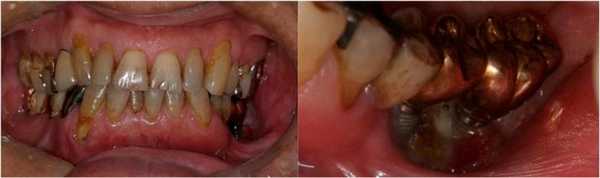

В ходе клинического исследования у пациента был обнаружен болезненный отек левой щеки и гипестезия нижней губы с левой стороны, при этом возможность открытия рта была ограничена до ширины полтора пальца, а вокруг дентальных имплантатов с левой стороны наблюдался некроз альвеолярной кости, воспаление слизистой и периодическое гноеотделение (фото 1).

Фото 1. Клиническая ситуация до лечения.

На ортопантомограмме контурировалась слабо демаркационная зона деструкции костной ткани в области имплантатов на месте 35 и 36 зубов, при этом поражение достигало нижнего края челюсти, что в результате спровоцировало возникновение патологического перелома. Вокруг имплантатов с правой стороны челюсти никаких патологических поражений отмечено не было (фото 2). С помощью КТ-сканирования удалось подтвердить деструкцию нижней челюсти слева и наличие линии перелома через всю толщу костной ткани (фото 3).

Фото 2. Ортопантомограмма пациента до лечения.